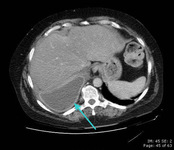

CT scan of chest showing empyema necessitans (long arrow), a chronic untreated empyema that has eroded through the thoracic cage and formed a subcutaneous abscess (short arrow)

From the collection of Dr Ami Rubinowitz; used with permission